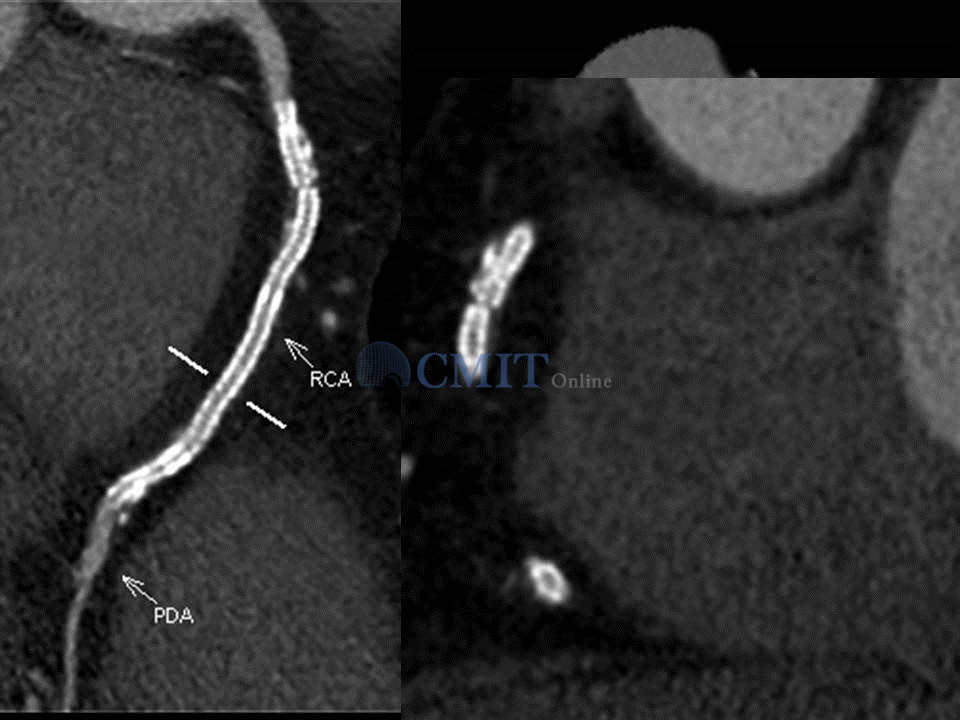

冠脉CTA读片技巧:如何判断支架内再狭窄?